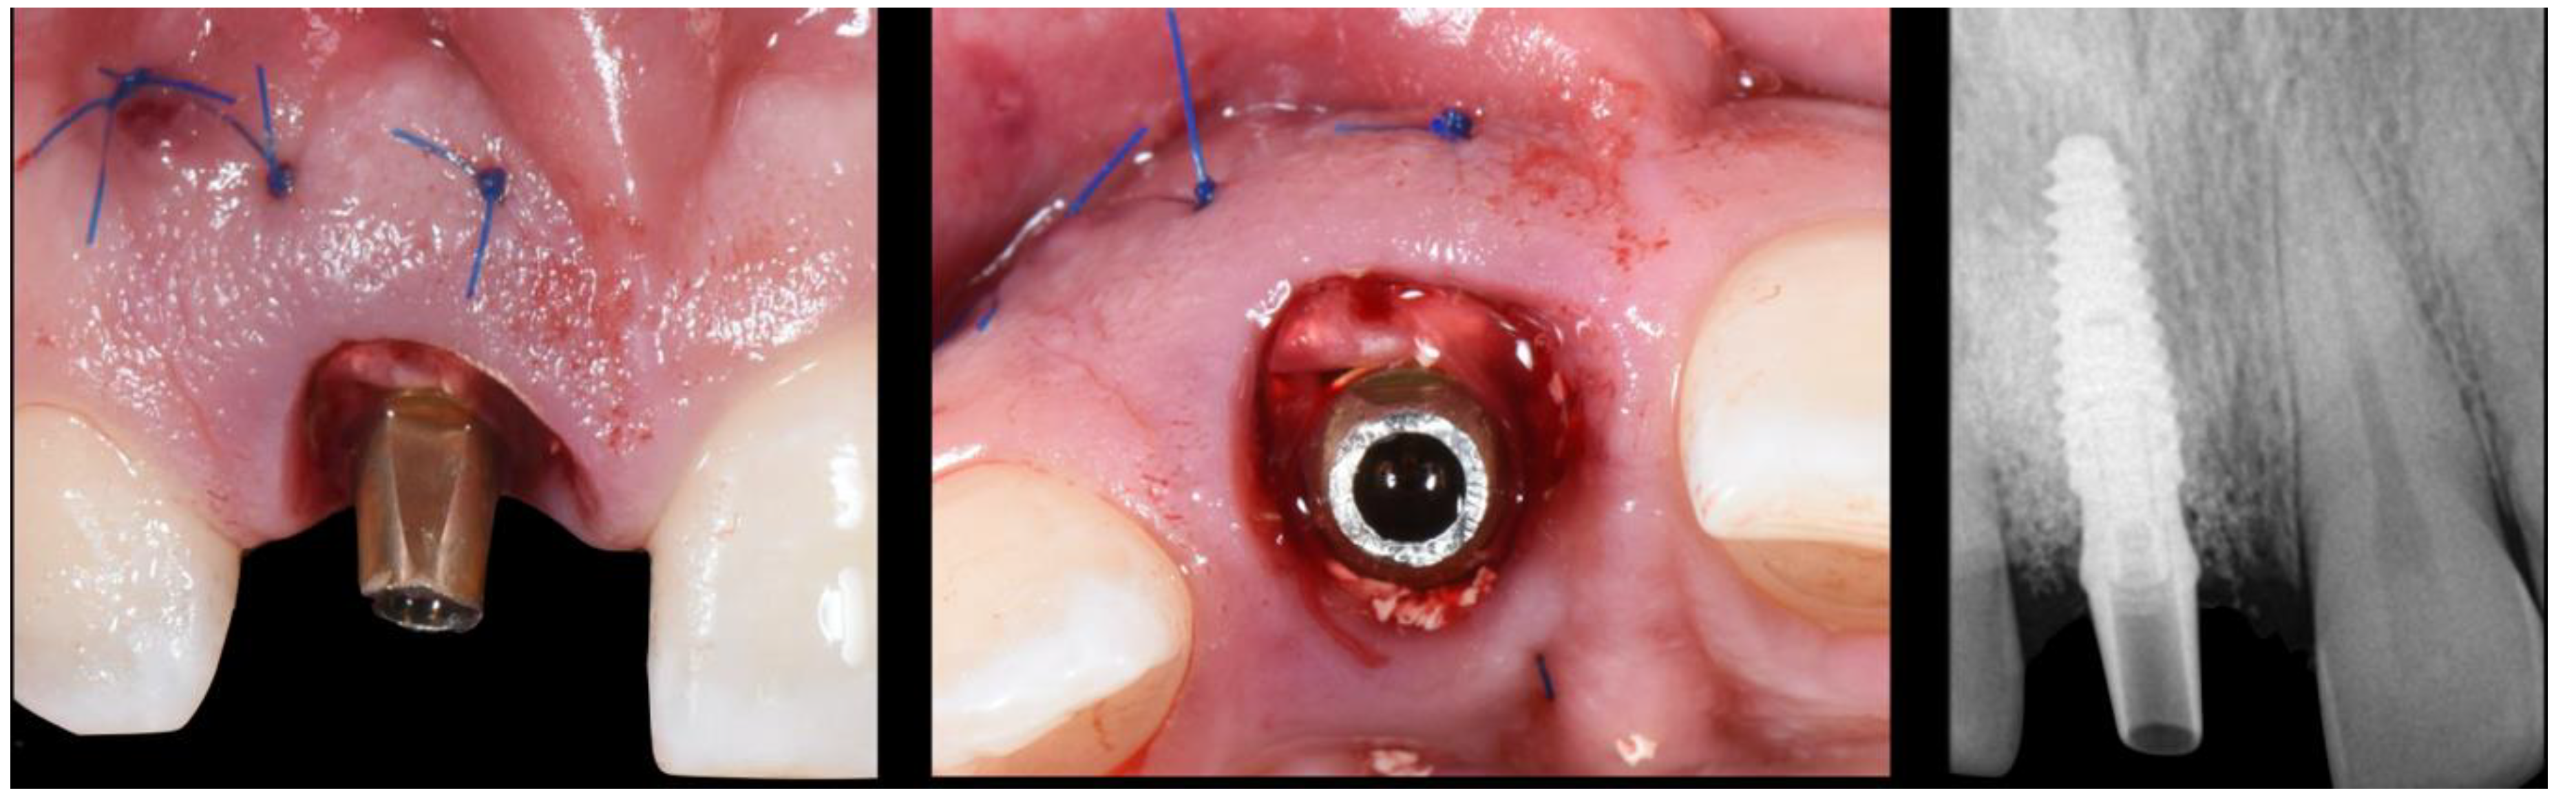

- (A)

- Supra-periosteal pouch design, demonstrating proper lateral and vertical extensions. The red lines demonstrate the pouch, while the yellow line demonstrates the mucogingival junction.

- (B)

- First abutment in place and membrane adaptation prior to BRG introduction.

- (C)

- Final relationship between first temporary prosthesis, abutment, and cervical gingival tissue.